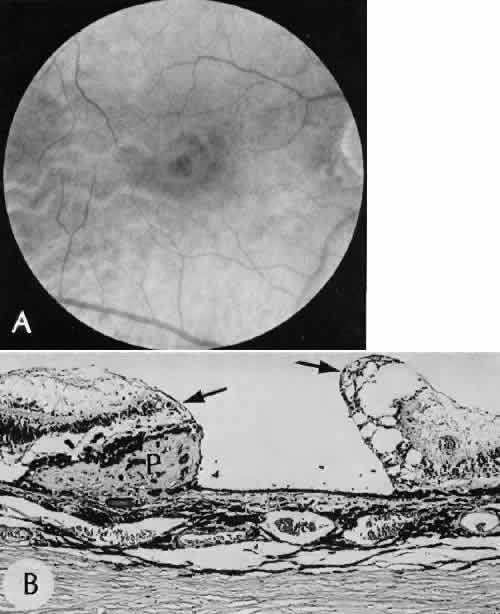

A flat anterior chamber is characterized by anterior displacement of the iris to near or in actual contact with the posterior surface of the cornea. The most common cause is leakage of aqueous along one of the suture tracks. Prolonged decompression of the anterior chamber increases the risk of synechiae formation and intractable secondary closed-angle glaucoma. Corneal endothelial damage may result in bullous keratopathy. Choroidal edema (choroidal hydrops or detachment) (Fig. 31) may be associated with a flat anterior chamber and may potentiate the condition. The choroidal edema will slow or stop aqueous production by the ciliary body, further delaying reformation of the anterior chamber. The histologic characteristics of choroidal edema consist of spreading of the choroidal tissue in a fanlike configuration and eosinophilic fluid filling the intervening spaces. The edema fluid may be lost in processing, leaving multiple apparently empty spaces.

Fig. 31. A case of choroidal detachment. A. By fundus reflex, a large dome-shaped mass can be seen originating from the choroid. The differential diagnosis would include uveal malignant melanoma. In this case, the clinical findings were due to choroidal detachment from the sclera because of fluid accumulating in the suprachoroidal space following cataract surgery. B. The histologic section from another case of choroidal detachment illustrates the location (arrow) and extent of the detachment. In this case the detachment extends to the region of the ciliary body limited anteriorly by the attachment of the choroid to the scleral spur. The displacement of the ciliary body will result in apparent shallowing of the anterior chamber. (Hematoxylin-eosin stain; × 6.)